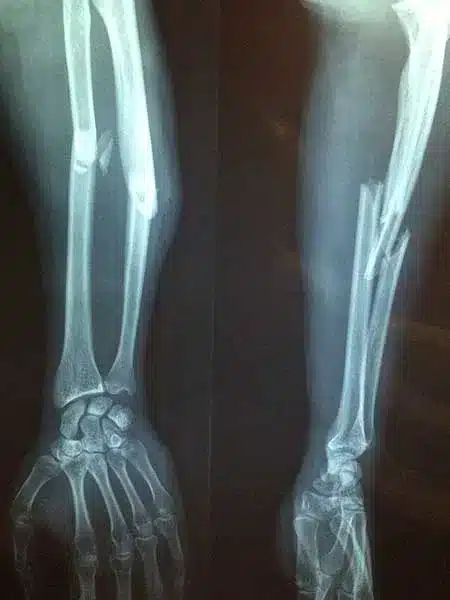

While these symptoms outline a broken bone, ultimately, x-rays are required to confirm the existence, type, and severity of a bone fracture.

Serious fall accidents, car accidents, or other serious injuries can push the bone beyond its breaking point. The severity of a fracture injury depends on factors such as the type of break, location, and whether the bone fragments remain aligned.